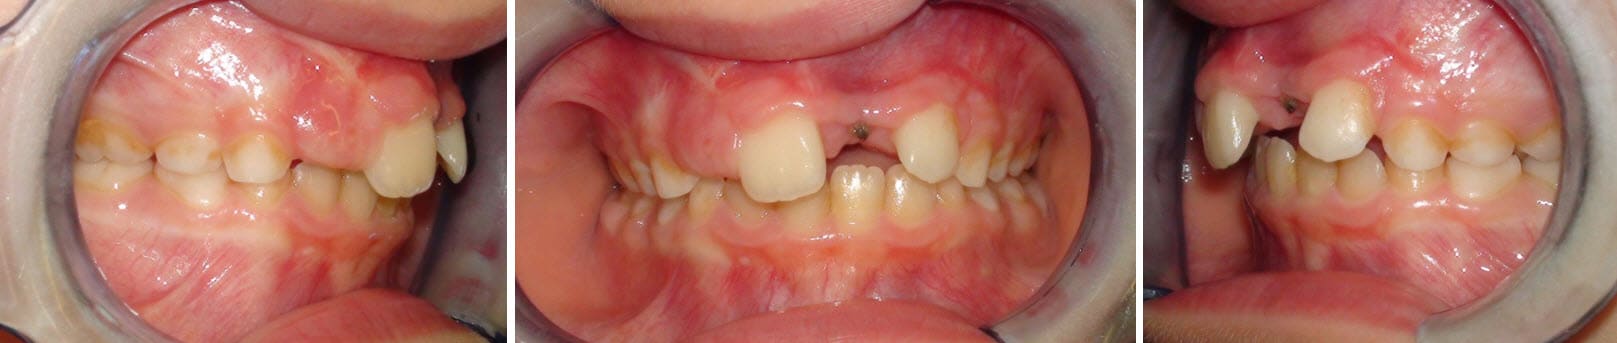

Deuxième cas :

Cette jeune fille vient de perdre (elle aussi) sa 21.

On image sa détresse...

On prévoit à terme de remplacer l'incisive manquante par un implant ou de fermer l'espace ?

Que lui dit-on et que faisons-nous dans l'immédiat ?

Elle est beaucoup plus jeune que la patiente précédente et à ce stade je ne pense pas qu'il soit possible de faire autre chose que d'attendre.

J'imagine que la solution n'est pas d'extraire la 12...

La 12 n'est déja pas présente et il y a surtout une tendance à la classe III ici.

La vestibuloversion de 11 et 22 et l'engrènement des secteurs latéraux, plus à droite qu'à gauche d'ailleurs. Je me trompe ?

Non pas moi.

Cl II overjet inc.

Utiliser la croissance mandibulaire dans un premier temps ?

Mais pas de suite. Et si incompétence mandibulaire.